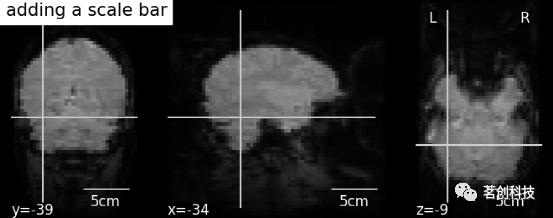

display.annotate(scalebar=True):添加比例尺。

display = plotting.plot_anat(mean_haxby_img,

title="adding a scale bar",

cut_coords=[-34, -39, -9])

display.annotate(scalebar=True)